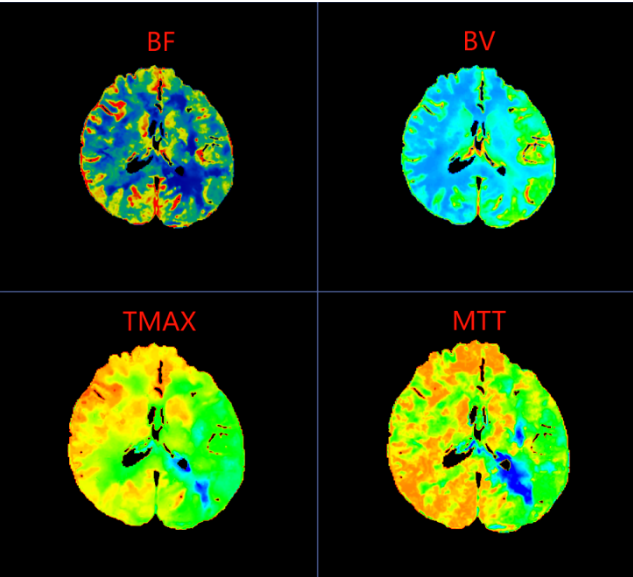

在脑梗死真正形成之前,大脑其实已经历一系列血流代偿与失代偿的过程。CTP(CT脑灌注成像)正是一种能够可视化脑血流动力学状态的前沿影像技术。它不仅能显示血管结构,更能精准评估脑组织的血流速度、血流量与血流通过时间,从而在患者尚未出现典型脑梗死症状时,就捕捉到脑灌注异常的“蛛丝马迹”。

2、CTP脑灌注成像:适用于疑似脑缺血前状态或短暂性脑缺血发作(TIA)患者,帮助评估脑血流储备与梗死风险。

4、多模态磁共振:包括DWI(弥散加权成像)、PWI(灌注加权成像)等,对超早期脑梗死具有极高敏感性,常用于急诊评估。